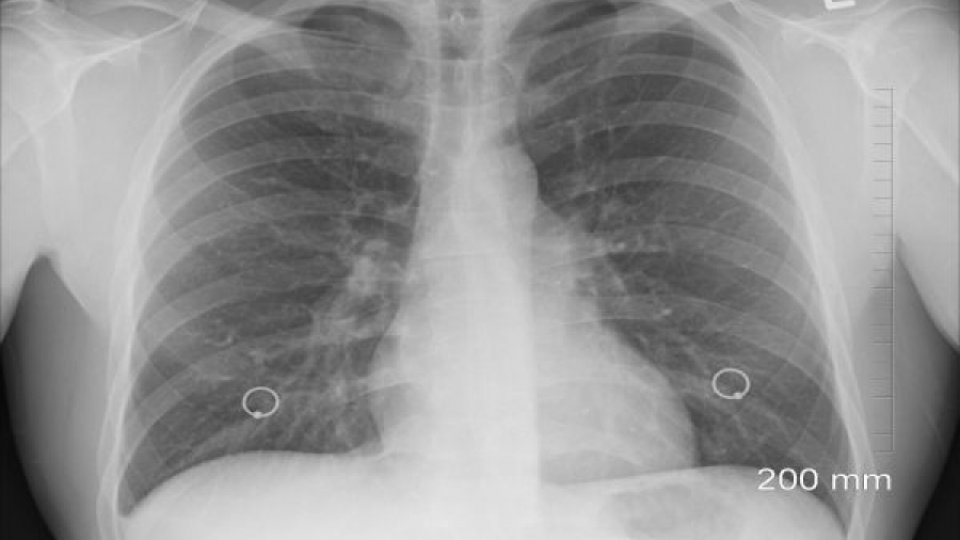

Potrivit sursei citate, activitatea de screening se va desfăşura prin deplasarea unei caravane mobile, un cabinet mobil dotat cu aparatură modernă de radiologie, instrumente de analiză şi depistare precoce a microbului tuberculozei, dar şi a altor 14 patologii.